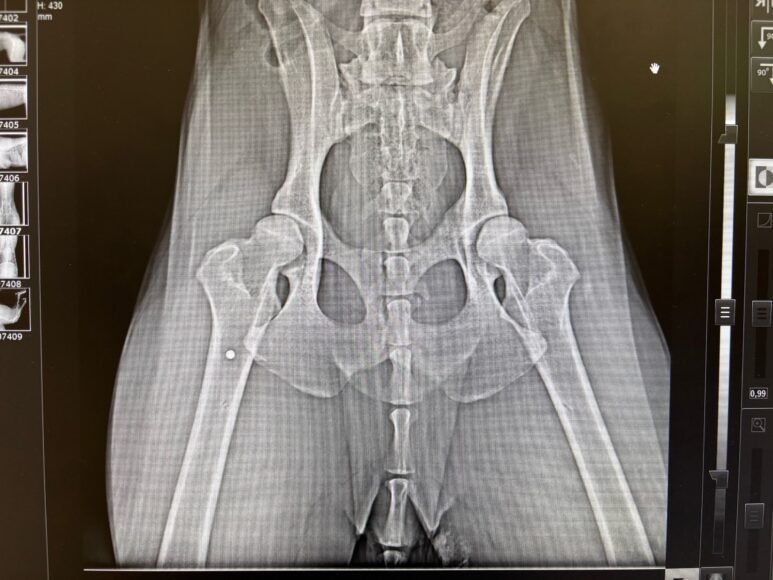

Мужчина по имени Вадим рассказал 78.ru, что отвел своих собак домой, а затем вернулся и при помощи шлейки кое-как вытащил пса, а затем передал волонтерам. Те отвезли его в выборгскую ветклинику, где рентген показал наличие дроби в позвоночнике и мягких тканях.

Позже Вадим нашел еще одну простреленную собаку, сучку, в поле и на этот раз сам отвез ее ветеринарам. И вновь на снимке медики увидели дробь.